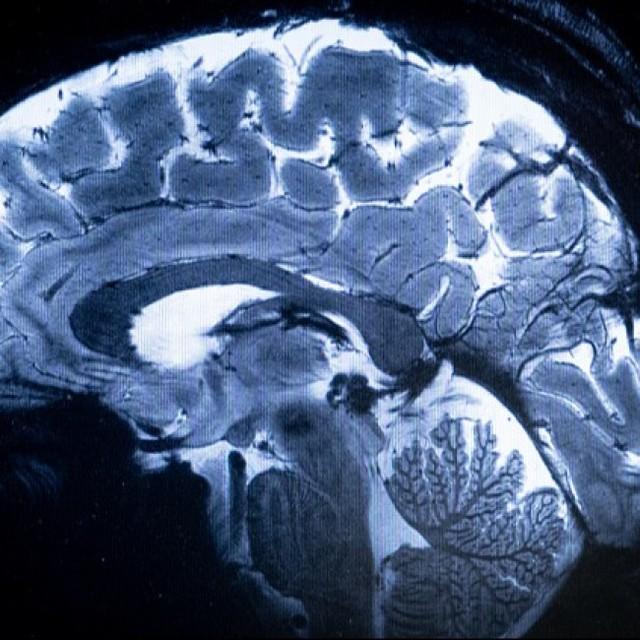

脳の断面図※イメージ画像